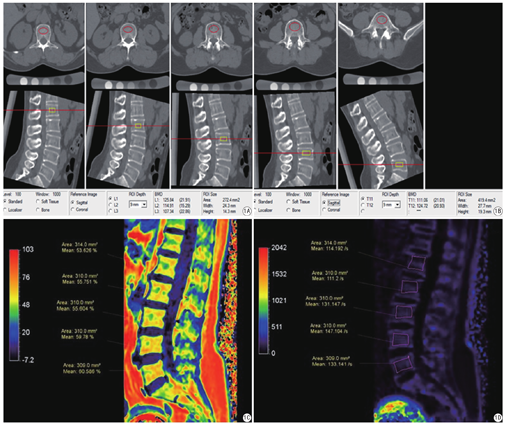

所有研究对象均接受东软NeuViz128排螺旋CT进行L1-L5扫描(电压:100 kV,电流25 mAs,螺距0.992,旋转时间0.5 s,层厚0.625 mm),扫描范围L1椎体上缘至L5下缘。将CT扫描图像传输至QCT分析工作站,采用美国Mindways公司QCT骨密度分析软件测量L1-L5椎体松质骨BMD (单位:mg/cm3),半自动设置感兴趣区,测量时注意避开骨岛、硬化和血管壁钙化(见图1A、图1B)。

用飞利浦Ingenia CX 3.0 T MRI设备行腰椎mDIXON-Quant检查。采用8通道腹部线圈。扫描参数:TR 8.0 ms,TE 1.45 ms,FOV:156 mm×360 mm,反转角3°,三维图像分辨率:2 mm×2 mm×6 mm,敏感度编码(sensitivity encoding,SENSE)为2,信号平均次数(number of signalaveraged,NSA)为1次,扫描时间20 s。测量图像选择经过腰椎体(L1-L5)正中矢状位,手工绘制感兴趣区测量FF(单位:%)、R2* (单位:/s),感兴趣区尽量在椎体最大层面的中心部分,避开无关部分,并根据不同椎体的大小调整感兴趣区面积大小,见图1C、图1D。